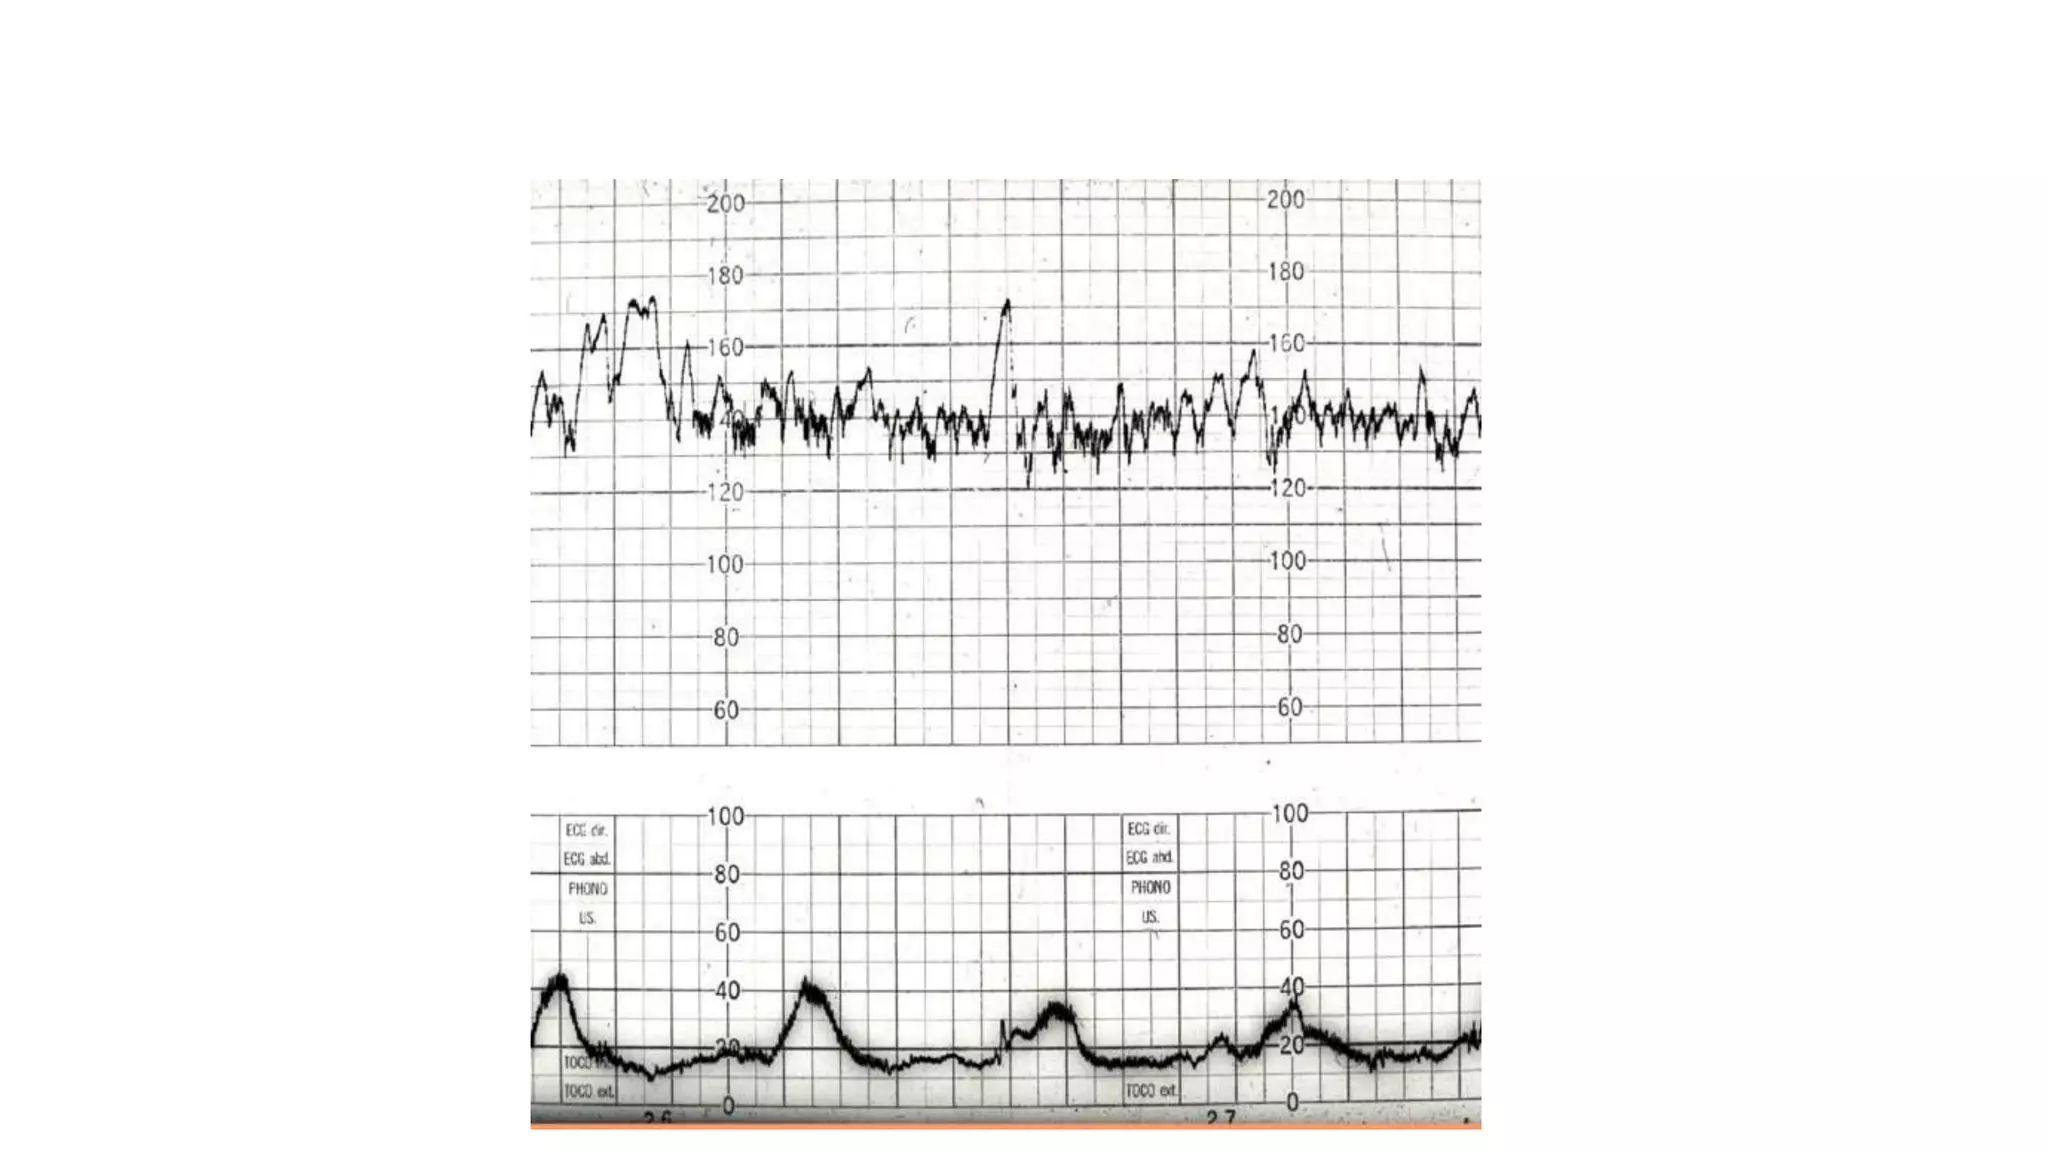

The document discusses key metrics for monitoring a baby's heart rate in utero, including the normal baseline rate of 100-160 bpm and variability. It also covers types of accelerations and decelerations that can occur, such as early or late, as well as bradycardia, which is an abnormally slow heart rate.